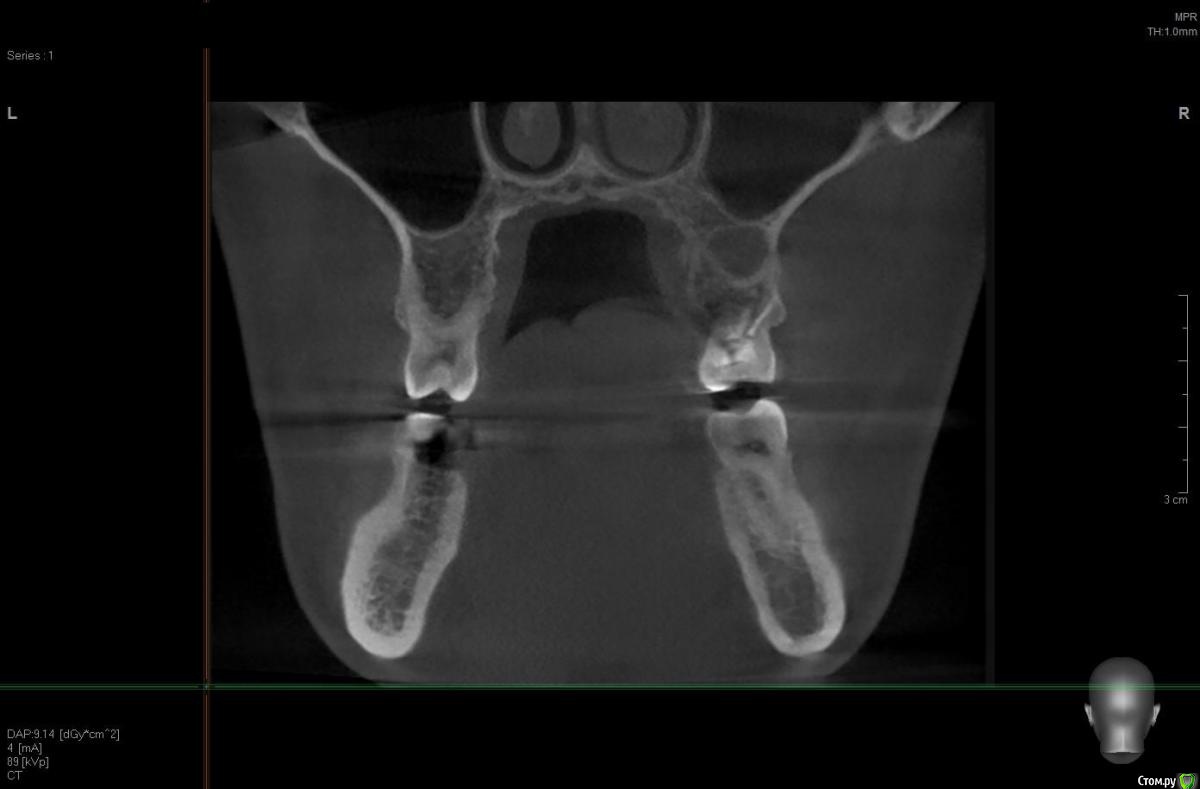

solitary Опубликовано 10 апреля, 2017 Поделиться Опубликовано 10 апреля, 2017 Доброго времени суток! Мое желание исправить прикус превратилось в ходьбу по врачам - от терапевта, до оториноларинголога и хирурга. На ОПТГ (прилагаю) ортодонту не понравилось темное пятно над верхней правой 6-кой. Т.к. хирурга у них в клинике нет, то на консультацию отправили к ортопеду-имплантологу. Предварительный диагноз - киста. Сделали КТ (скриншоты прилагаю).Диагноз подтвердили, но на всякий случай отправили к ЧЛ-хирургу. Тот с КТ от Пикассо не работает (компьютер слабый), но по моим скриншотам также считает, что это киста. Стоматолог врач-терапевт высшей категории вскрыла пломбу и увидела хорошо пролеченные каналы, плюс сделала прицельный снимок 6-ки, который кисту в зоне корня зуба не выявил (даже намека нет). Хотят отправить к оториноларингологу, так как, если верить КТ, киста у границы гайморовой пазухи и консультация ЛОР-врача будет не лишней. Хотелось бы послушать мнение опытных хирургов.-------ОПТГ http://radikal.ru/big/hq2s2k2k9uadn Ссылка на комментарий

Irouil Опубликовано 10 апреля, 2017 Поделиться Опубликовано 10 апреля, 2017 Киста есть. Лор не при чем. Вскрытие пломбы вообще не при чем. Ну а прицельные снимки (после КТ) - ни о чем. 2 Ссылка на комментарий

колесников Опубликовано 10 апреля, 2017 Поделиться Опубликовано 10 апреля, 2017 Читаю и все больше удивляюсь. Место действия Москва?Удаляйте в плановом порядке,пока дно гайморовой пазухи не вскрыто кистой. В случаях схожих с вашим,рекомендую пациентам совместить удаление с одномоментной имплантацией,пока ещё условия позволяют. 2 Ссылка на комментарий

Irouil Опубликовано 11 апреля, 2017 Поделиться Опубликовано 11 апреля, 2017 Повторюсь - вскрытие пломбы не при чем. Киста в кости, пломба в зубе. Между кистой и пломбой - закрытый наглухо (судя по кисте у корня - не совсем наглухо) длинный корневой канал. Навряд кто-то возьмется лечить этот зуб гарантийно. Но если Вы готовы рисковать своим временем и финансами - шансы есть. Ссылка на комментарий

Bier Опубликовано 11 апреля, 2017 Поделиться Опубликовано 11 апреля, 2017 Лечить конечно. Не вижу тут 100% показаний к удалению. Есть желание сохранить - найдите эндодонтиста с микроскопом и лечите. 2 Ссылка на комментарий